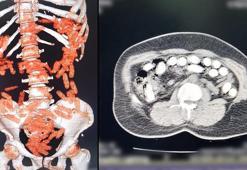

Yabancı uyruklu 2 şüphelinin midesinden 1 kilo 340 gram afyon sakızı çıktı

Yabancı uyruklu 2 şüphelinin midesinden 1 kilo 340 gram afyon sakızı çıktıBitlis'te yol kontrolü sırasında gözaltına alınan yabancı uyruklu 2 şüphelinin çekilen röntgenlerinde, midelerinde 1 kilo 340 gram afyon sakızı tespit edildi. Yutulan 96 kapsül, tıbbi müdahale ile çıkarıldı.

Yolcunun midesinden 1 kilo 134 gram Afyon sakızı çıktı

Yolcunun midesinden 1 kilo 134 gram Afyon sakızı çıktıErzurum'da, yolcu otobüsünde şüphe üzerine hastanede röntgeni çekilen yolcunun midesinde Afyon sakızı, tespit edildi. Yolcu, midesindeki 1 kilo 134 gram Afyon sakızını doğal yollarla çıkardı.

Midesinden yaklaşık 1 kilo uyuşturucu çıktı

Midesinden yaklaşık 1 kilo uyuşturucu çıktıKayseri'de, polisin düzenlediği uyuşturucu operasyonunda 2 kişi yakalandı. Şüphelilerden birinin midesinden 88 kapsül halinde 974,52 gram afyon sakızı çıktı.